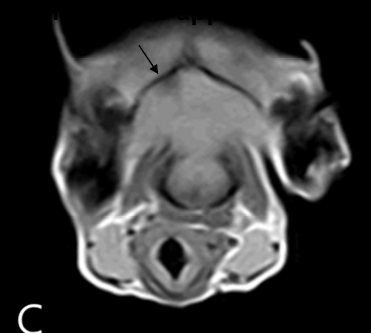

| MRI | |

|---|---|

![]() T1 (fluid๊ฐ ๊ฒ๊ฒ) | T2 (fluid๊ฐ ํ์๊ฒ) | - ๋๋ ๊ณ ๋(sulcus)์ด ๋งค์ฐ ์ ๊ด์ฐฐ๋จ : ๋๋ ์์ถ - Lateral ventricle์ด ์ ์๋ณด๋ค ํจ์จ๋ ํ์ฅ๋จ. - ๊ฐ๋๋ฆฌ๋์ ํฌ์ฌํ๋, tumor ๋ถ๋ถ์ด ํ์๊ฒ ์กฐ์๋จ. - Dural tail signs : tumor๊ฐ meninges(๋์๋ง) ๋ถ๋ถ์ ๊ผฌ๋ฆฌ์ฒ๋ผ ์ฐ๊ฒฐ๋์ด ์์. (๋์๋ง์ dura mater์ ์ฐ๊ฒฐ๋์ด ์๋ ๊ฒ) โ Dural tail sign์ด ๊ด์ฐฐ๋๋ฉด ๋ฐ๋ก meningioma๋ก ํ์ ๊ฐ๋ฅ. โ Intracranial meningioma |

![]() T1-enhanced | - Diencephalon ๋ถ๋ถ์ ํผ์งํ ์ข

์ - ์ ๋ฐ์ ์ผ๋ก ๋์ ์์ถ ์๊ฒฌ - ์๋์ cyst๋ก ์ถ์ ๋๋ ๋ถ์๋ ์์ - CDS๋ ๋๋ฐ๋จ, but ๋น์์๋ ๋จ์ meningioma๋ก ์ง๋จํจ. * Tumor์ ์ํด ๋์ ์ฆ๊ฐํ๋ฉด โ Cushing reflex๋ฅผ ๋ณด์ผ ๊ฐ๋ฅ์ฑ ๋์. |

- Intracranial meningioma

- lomustin (BBB๋ฅผ ํต๊ณผํ๋ ํญ์์ ) ์ฒ๋ฐฉ โ ์ฆ์ ์ํ, 1๋ ์ด์ ์์กด.